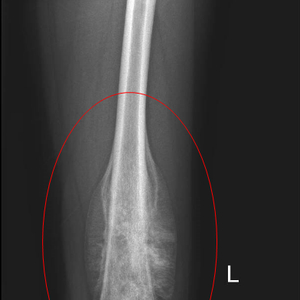

转自:春立在线

患者男性,14岁,患者在活动时出现左膝关节疼痛,以为是肌肉扭伤,没有在意,但1个月期间就出现疼痛加重并膝关节活动受限,不能忍受,5月在就近医院就诊后检查发现左股骨下段严重骨破坏并伴软组织肿物,考虑为恶性,这一结果对孩子家长来说无异于晴天霹雳,于天津多家三甲医院就诊咨询后,患者慕名来到了天津市肿瘤医院骨与软组织肿瘤科门诊,找到了杨蕴主任。经检查,肿瘤固定于左股骨下段,四周没有边界,压痛明显,左下肢活动困难,结合影像学检查,考虑为青少年典型骨肉瘤。经过术前新辅助化疗后,患者肿瘤边界清楚,具备保肢手术条件。

术前影像